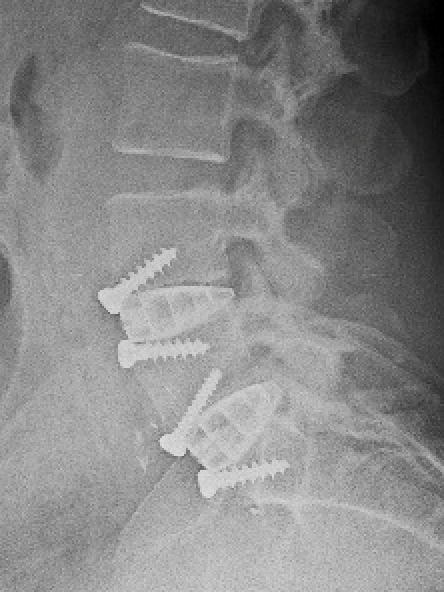

Colonne vertébrale lombaire / Rachis lombaire